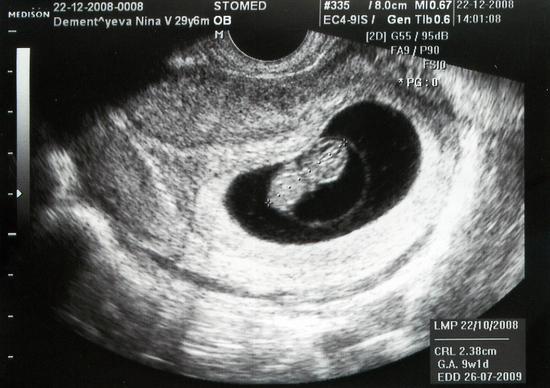

Ультразвуковое обследование – современной, практичный и безвредный способ исследования женщины во время беременности. УЗИ обычно назначают:

- для подтверждения зачатия;

- для выявления возможных дефектов и отклонений развития плода, а также осмотра расположения плаценты;

- для установления срока беременности;

- для определения жизнеспособности и пола эмбриона.

В некоторых случаях применение УЗИ особенно необходимо – процедура поможет проверить течение беременности, своевременно выявить отклонения, а также сохранить жизнь и здоровье будущей матери и ее ребенка.

Специалисты уверены, что плановое осуществление ультразвукового обследования для выявления отклонений во время вынашивания ребенка не угрожает какими-либо вредными последствиями для здоровья.